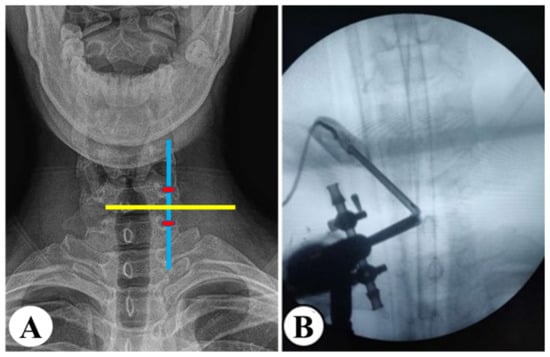

2.3.1. UBE

2.3.2. PE